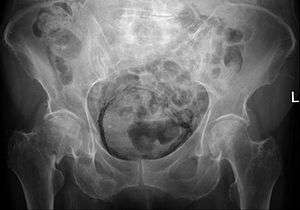

Emphysematous cystitis